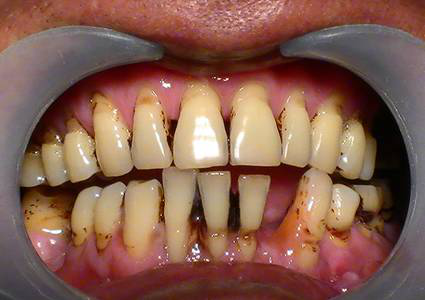

牙齦周?chē)摺⒀澜Y(jié)石大量堆積,細(xì)菌大肆滋生刺激牙齦,引發(fā)炎癥,導(dǎo)致牙齦萎縮、牙齒松動(dòng)、移位等問(wèn)題,牙齒看上去就感覺(jué)像變長(zhǎng)了。

成年人多少都患有牙周疾病,但因進(jìn)展緩慢常常忽略,發(fā)現(xiàn)問(wèn)題時(shí)已到“牙周病末期”了,雖然可以通過(guò)牙周治療去除牙結(jié)石,緩解炎癥,但萎縮的牙齦卻再也找不回來(lái)了。

很多人不及時(shí)治療,都會(huì)發(fā)展成下面這種情況↓

預(yù)防:防止牙周病_好的辦法就是每半年到1年定期洗牙一次,洗牙是有效去除牙結(jié)石的唯一辦法。

治療:如果已經(jīng)患了牙齦萎縮的朋友,需要盡早進(jìn)行牙周刮治,將牙齦邊的牙結(jié)石清除干凈,雖然之前的牙齦很難救回來(lái)了,但防止它繼續(xù)萎縮下去也是非常必要的。